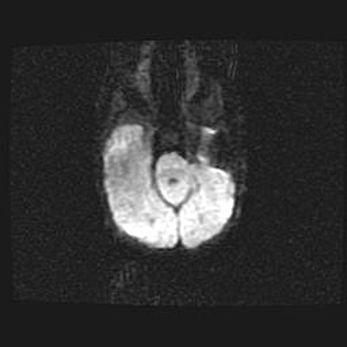

Сообщающаяся гидроцефалия. Кистозная энцефаломаляция головного мозга.

Возраст: 3 месяца 4 дня

Вес: 3100 г

Пол: женский

Окружность головы: 34 см

Срок гестации: 31 неделя

Кистозная энцефаломаляция головного мозга - одна из форм поражения головного мозга в детском возрасте. Характеризуется возникновением множественных и распространённых кист в коре, белом веществе и подкорковых образованиях головного мозга у плодов, новорождённых и детей раннего возраста. Развитие кистозной энцефаломаляции связано с внутриутробной асфиксией и гипотонией, родовой травмой, тромбозом синусов, пороками развития сосудов, инфекциями, сепсисом и другими причинами. Наиболее значимые инфекционные агенты: вирусы простого герпеса, цитомегалии, краснухи, токсоплазмы, энтеробактерии, золотистый стафилококк и другие.